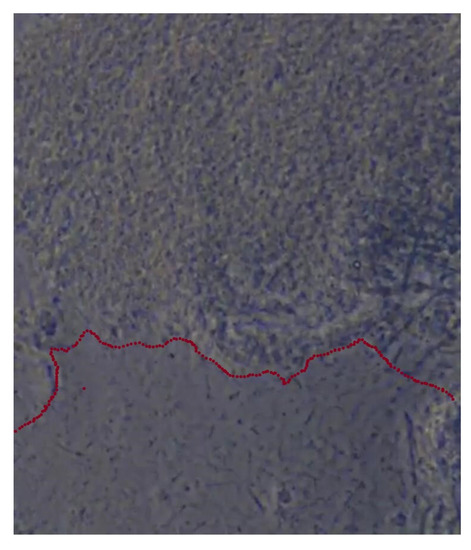

The sample was divided in two groups: Group A underwent metal multibracket self-ligating therapy (American Orthodontics, Sheboygan, WI, USA) [Figure 1a], and group B used clear aligners (Ortobel System, Bergamo, Italy) [Figure 1b]. These patients wore the aligners 22 h a day and replaced them every 14 days. Patients with multibracket self-ligating appliances combined the use of orthodontic brush, interdental brushes, and one-tuft brushes; patients in therapy with aligners used soft brushes and dental flosses. Dental floss was not recommended for patients with multibracket therapy because, due to orthodontic floss, it would have been difficult to use.

Figure 1. (a) Group A: patients with multibrackets. (b) Group B: patients with aligners.